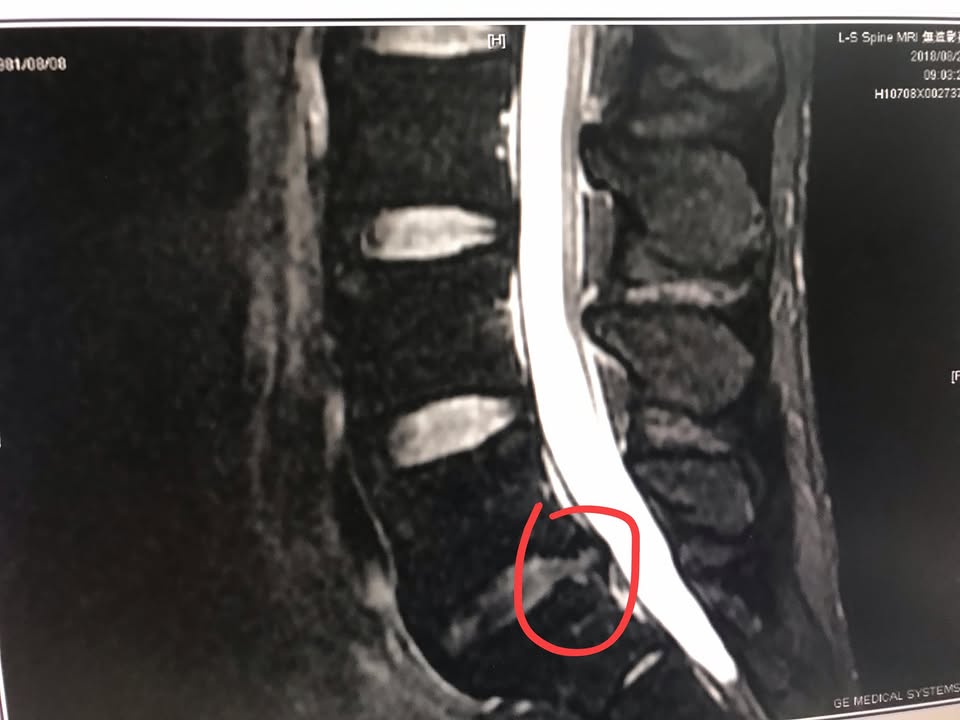

從今年八月多拍的片子可以發現第五腰椎間盤突出且壓迫到左側神經根,所以他表現出大小便上廁所的強烈疼痛,治療的原理與思維放在下面影片來表示